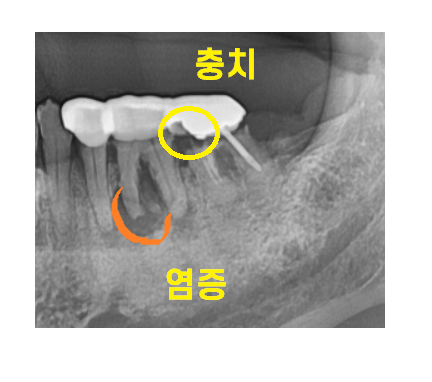

오래전 하신 은니가 문제였는데요.

23.05.22

오래 쓰셨습니다.

문제가 되는 치아를 뽑고

뼈이식을 해두었어요.